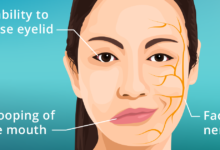

تومور بدخیم مغزی نوعی از سرطان است که در بافتهای مغز یا نخاع رشد میکند. این تومورها شامل سلولهای غیرطبیعی هستند که به سرعت تکثیر شده و میتوانند به نواحی دیگر مغز یا حتی بدن گسترش یابند. برخلاف تومورهای خوشخیم، تومورهای بدخیم مغزی بسیار تهاجمی بوده، به سرعت رشد میکنند و به بافتهای مجاور تهاجم میکنند.